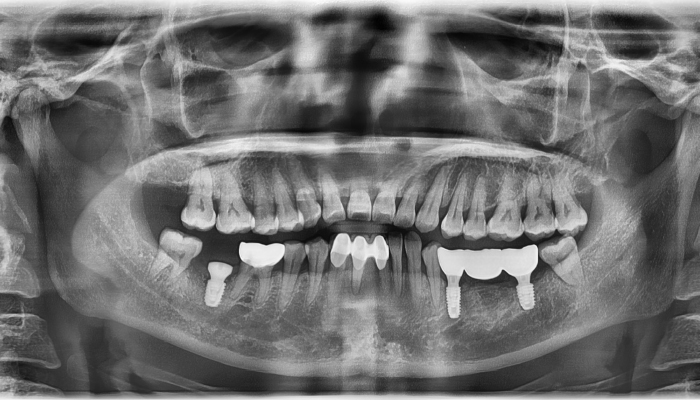

• 식립전

식립후